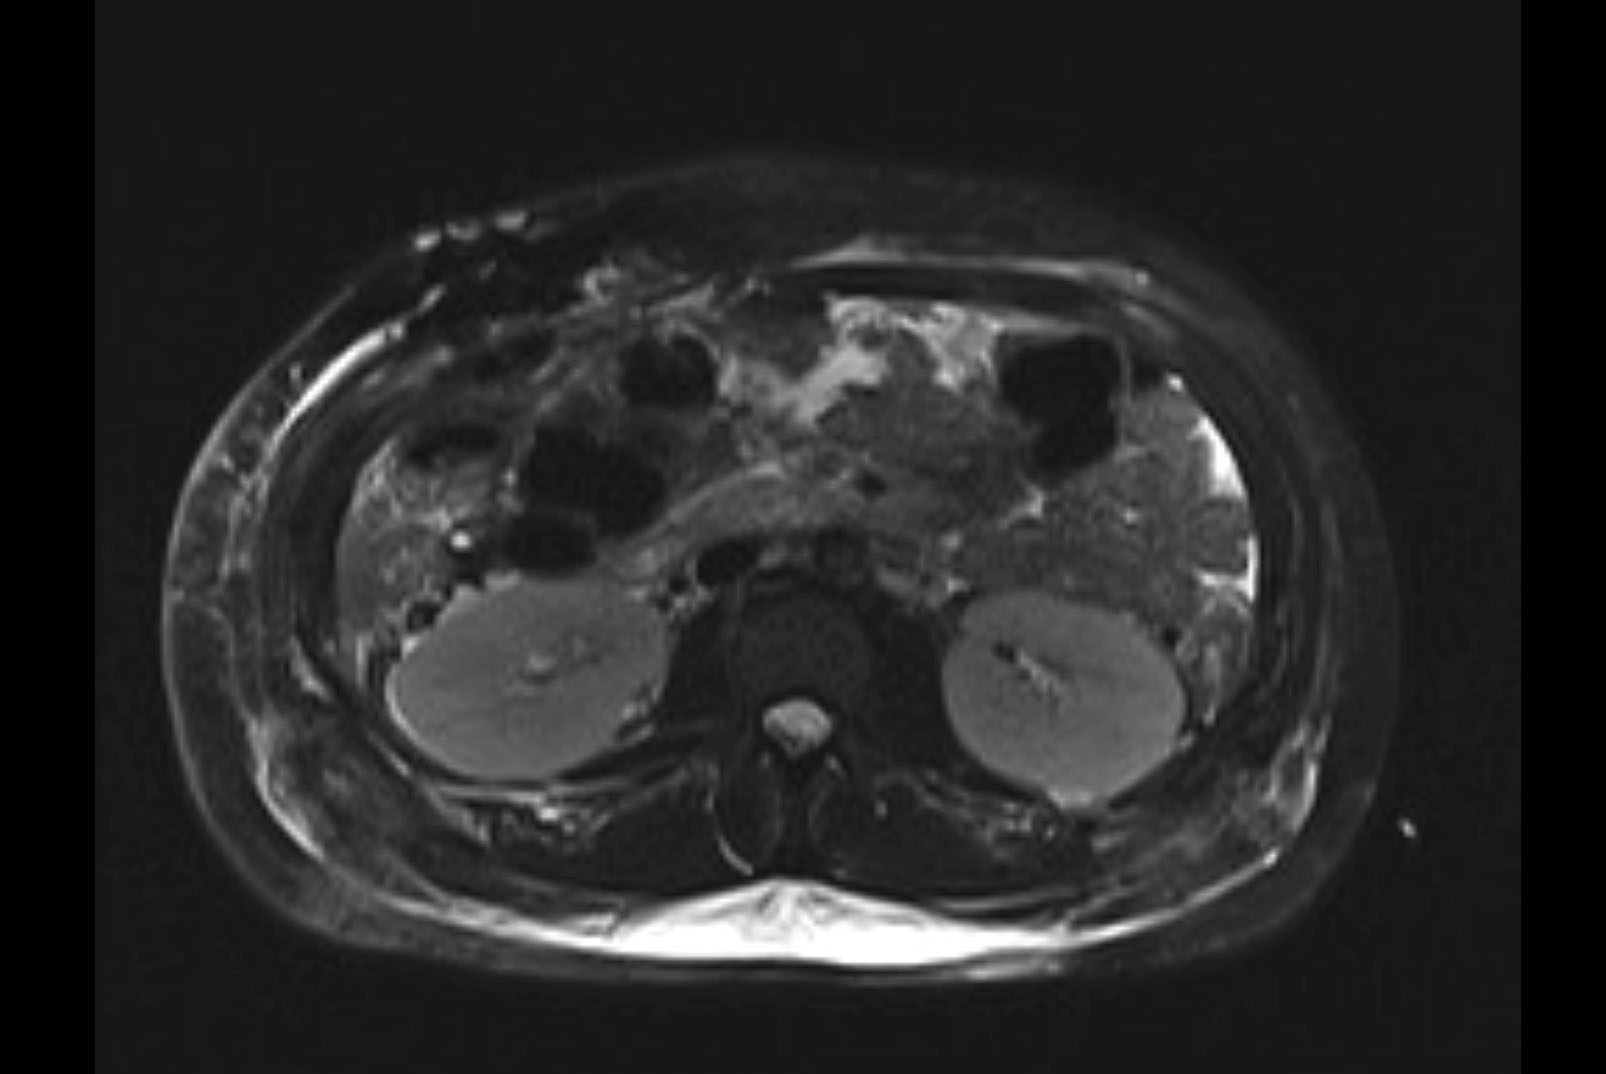

Imaging Analysis

Look through the patient's CT scan to identify any areas of concern for the necessary procedure.

MRI T1

Based on initial findings, which issue(s) would you be most concerned about?